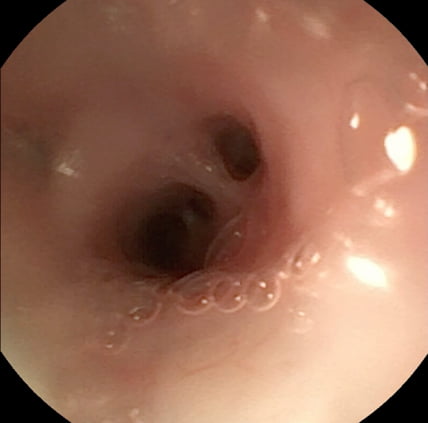

同一症例のレントゲン検査と気管支鏡検査

鼻咽頭狭窄の治療前と治療後